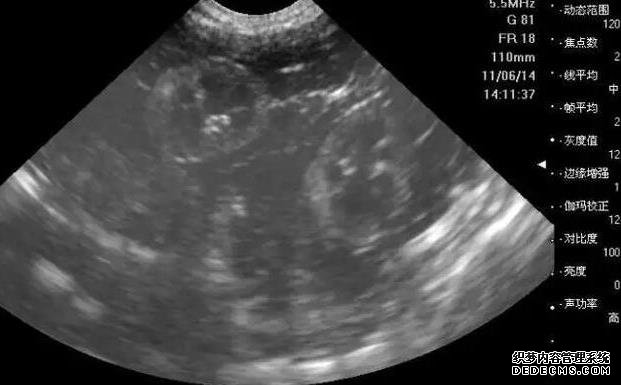

2、明確精液情況:檢查男方是否有足量、健康符合生育要求的精子,了解精子的數量和活動度等。如果精子正常,無需繼續檢查。如果精液質量異常,需要繼續查明原因,例如B超、性激素、染色體等,具體要根據醫生安排進行。

3、腹部彩超檢查:通過B超確定子宮內部環境是否正常,如大小形態如何、是否存在宮腔疾病,子宮內膜是否適合著床等。